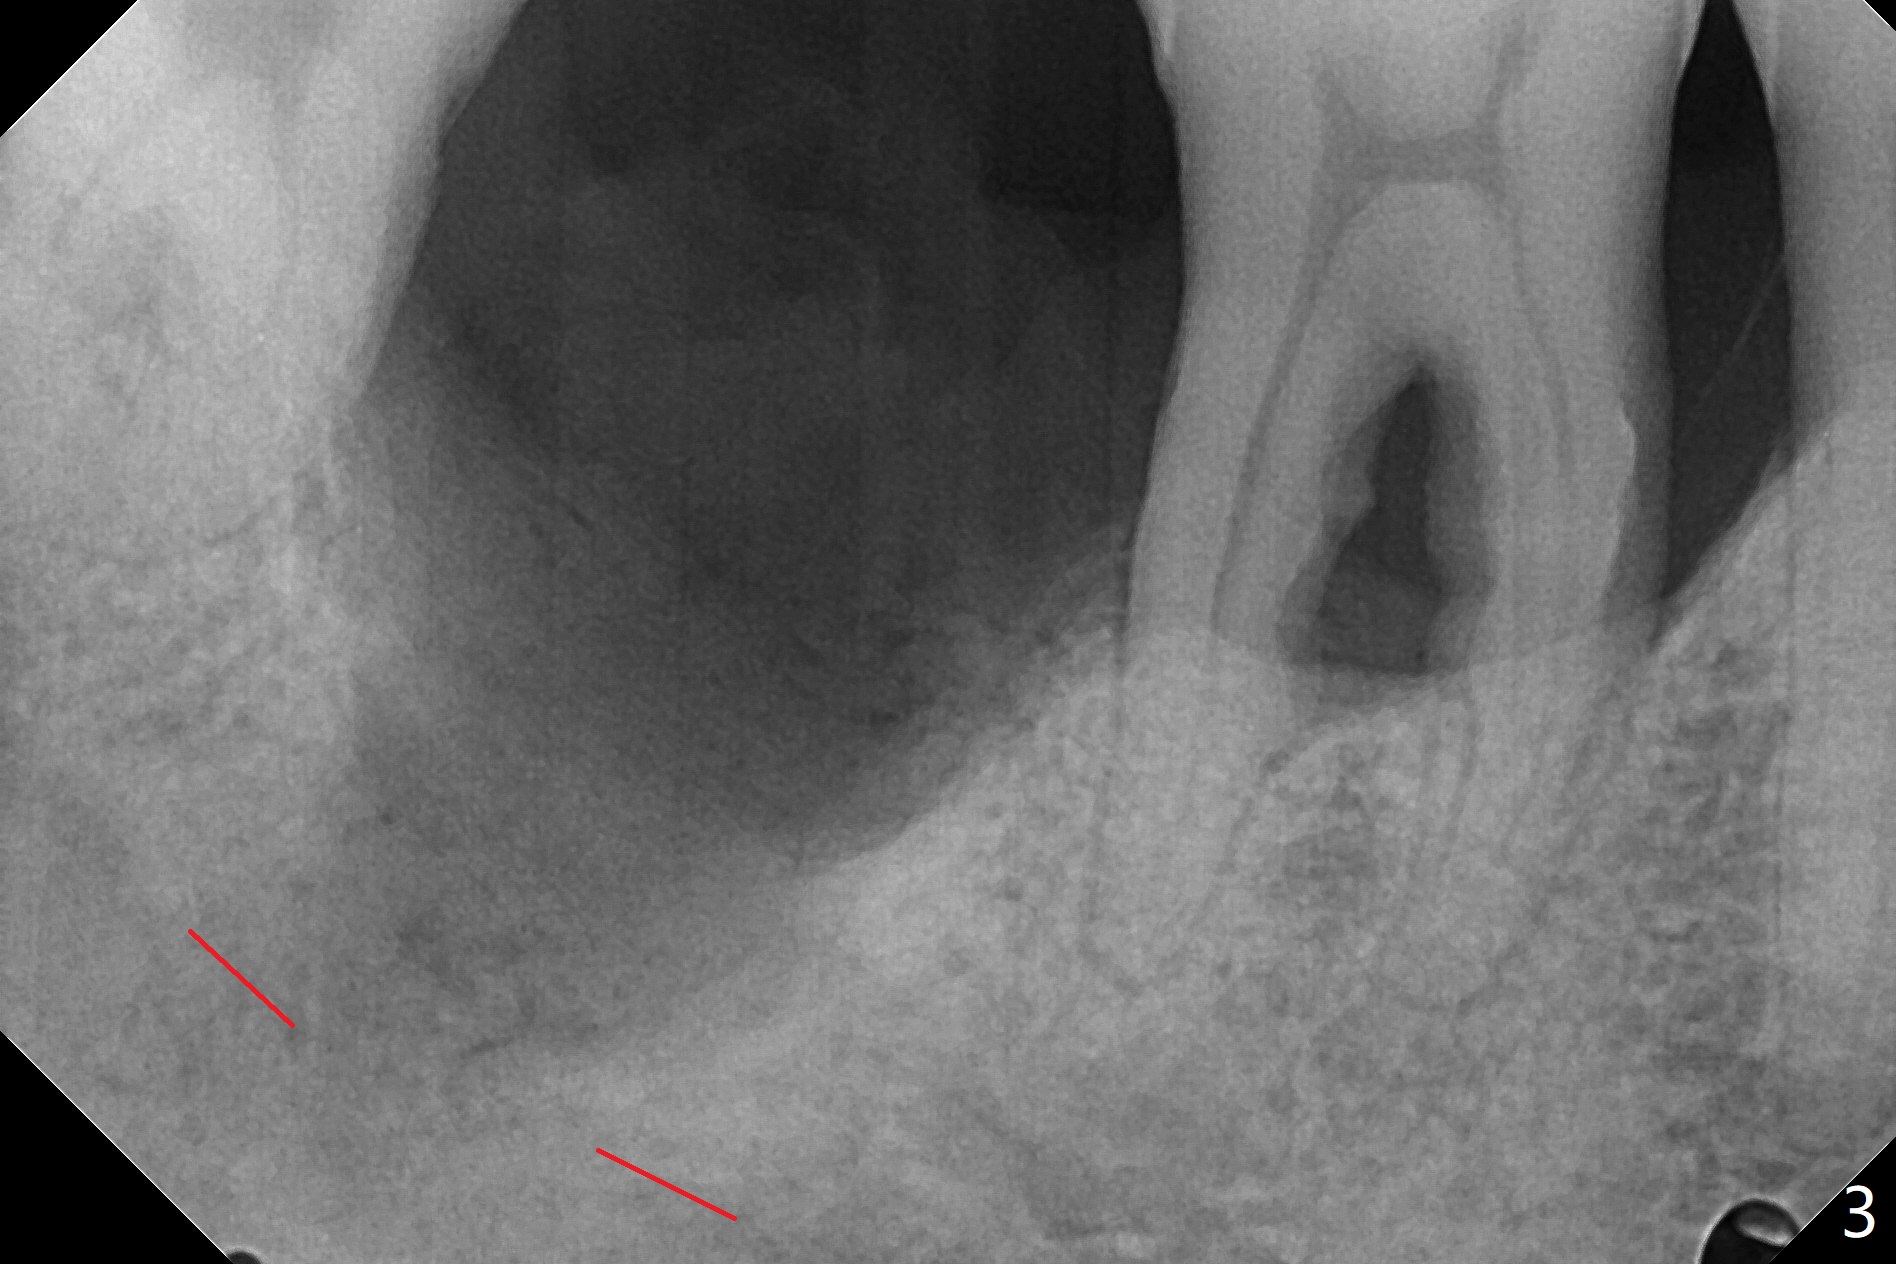

40岁男,牙周炎(图一,4年前拍摄),现在要求拔除31号牙,劝导后同意植骨,问题在于牙根长(图二),可能接近神经(红虚线)。拔牙后,舌侧骨板缺失,不敢大胆在根尖清创,术中拍摄根尖片(图三),牙槽窝根尖接近神经管,最后可能遗留些根尖肉芽组织(图四:*(最好拍摄CT))。粘性骨粉表面覆盖PRF和Cytoplast,使用4-0 PTFE缝线,没有使用牙周敷料,因为后者往往与缝隙粘连,脱落时缝线必须撤除,可能影响不可吸收膜固定。不过这次不可吸收膜术后四天脱落,术后五天骨粉好像丢失不多(图五),可能与粘性骨粉有关。下次需要牙周敷料,牙齿长,敷料固定好。Return to Protect Graft 19 位点保存 Xin Wei, DDS, PhD, MS 1st edition 06/28/2021, last revision 07/09/2021